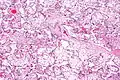

| Micrograph of villous immaturity. H&E stain. | |

Immature chorionic villi are larger and have more central blood vessels; thus, the diffusion distance for gas and nutrient exchange is larger and, therefore, placental function is impaired.